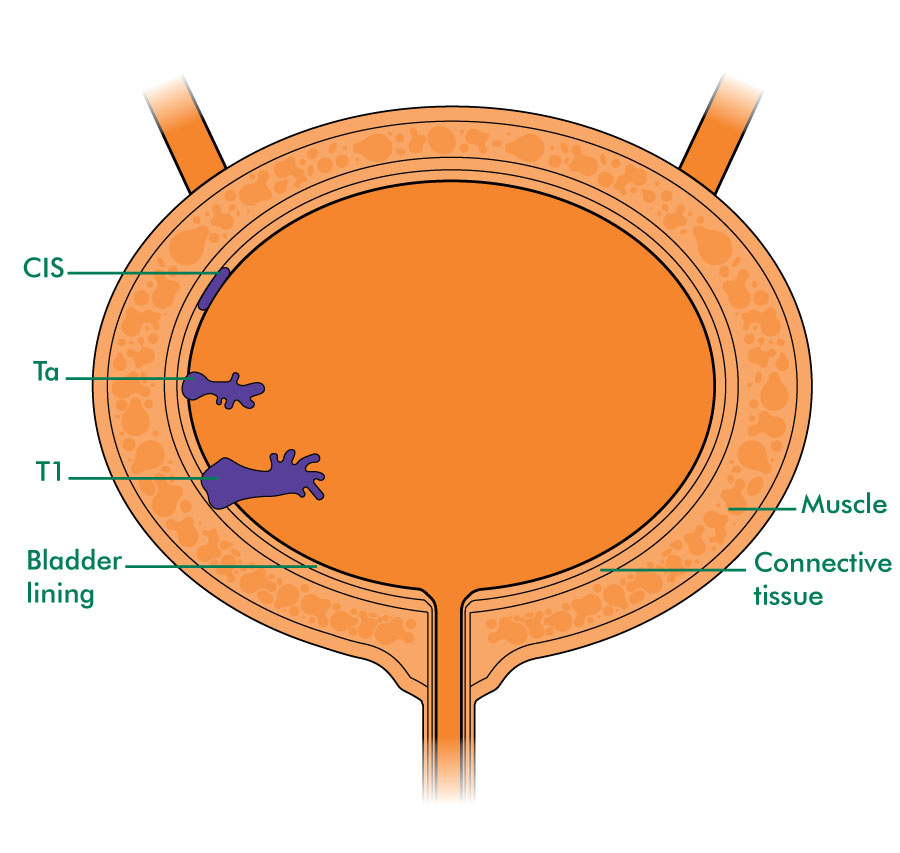

Illustration of different pathological stages of bladder cancer. Stage …

Stages of bladder cancer from Meyer et al., (2002). Bladder cancer can …

Overview of staging and grading of bladder cancer tumor. The figure was …